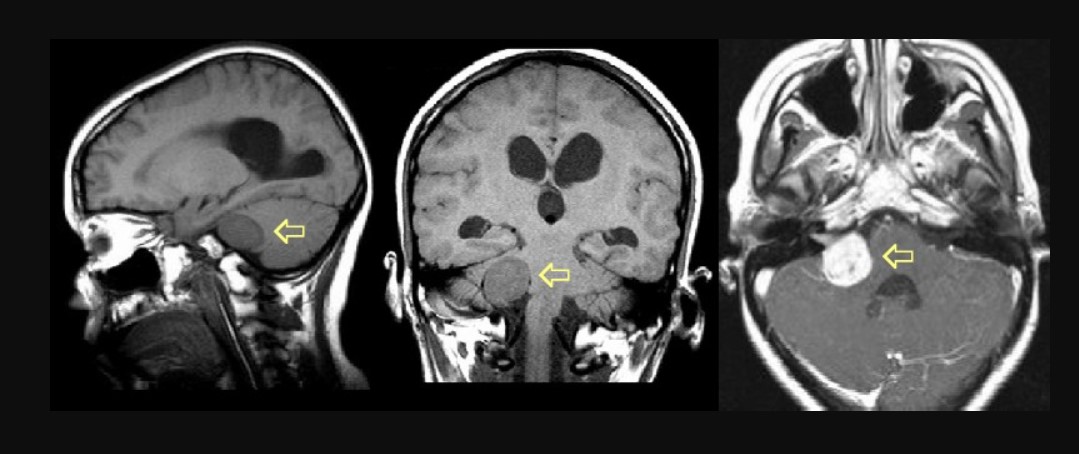

Методом вибору для підтвердження діагнозу є магнітно-резонансна томографія головного мозку з контрастуванням. МРТ дозволяє виявити навіть невеликі пухлини у внутрішньому слуховому проході та оцінити поширення невриноми у мостомозочковий кут. Дослідження також допомагає визначити компресію мозочка, стовбура мозку або інших черепних нервів.

Невринома (вестибулярна шваннома) - це доброякісна пухлина, що формується з клітин шваннівської оболонки вестибулярної частини переддверно-завиткового нерва. Пухлина зазвичай росте повільно, але може поступово здавлювати слуховий нерв, стовбур мозку та інші структури мостомозочкового кута.

Найчастіше пухлина виникає у вестибулярній частині переддверно-завиткового нерва у ділянці внутрішнього слухового проходу. З ростом невринома поступово виходить за межі слухового каналу та поширюється у мостомозочковий кут - анатомічний простір між мозочком і стовбуром мозку.